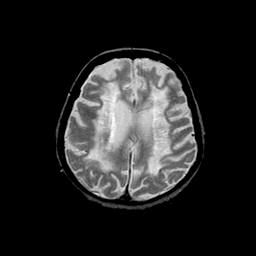

Basal Ganglia Calcification: T2-weighted MR -- Slice #12

[Home][Help][Clinical] Slice 12